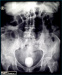

Abbildung 2: Harnblasenkonkrement 6 x 5 x 4 cm großes Harnblasenkonkrement nach spontanem Steinabgang |

Abbildung 2: Harnblasenkonkrement

6 x 5 x 4 cm großes Harnblasenkonkrement nach spontanem Steinabgang |